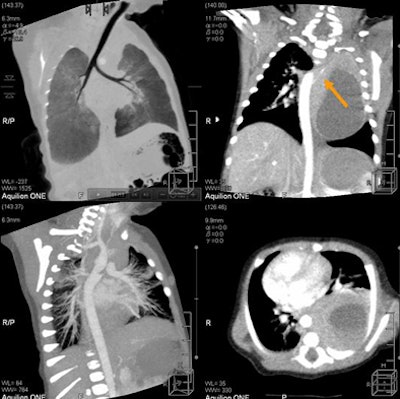

| Patient with stridor and giant cervical hemangioma was breathing continuously and not sedated during 320-detector-row CT, acquired in two rotations at 0.35 sec, 80 kV, 20 mA, and dose of 0.3 mSv. Below, additional rotation allows reconstruction of images at multiple time points, revealing air trapping that would have been missed at single-rotation scan. |